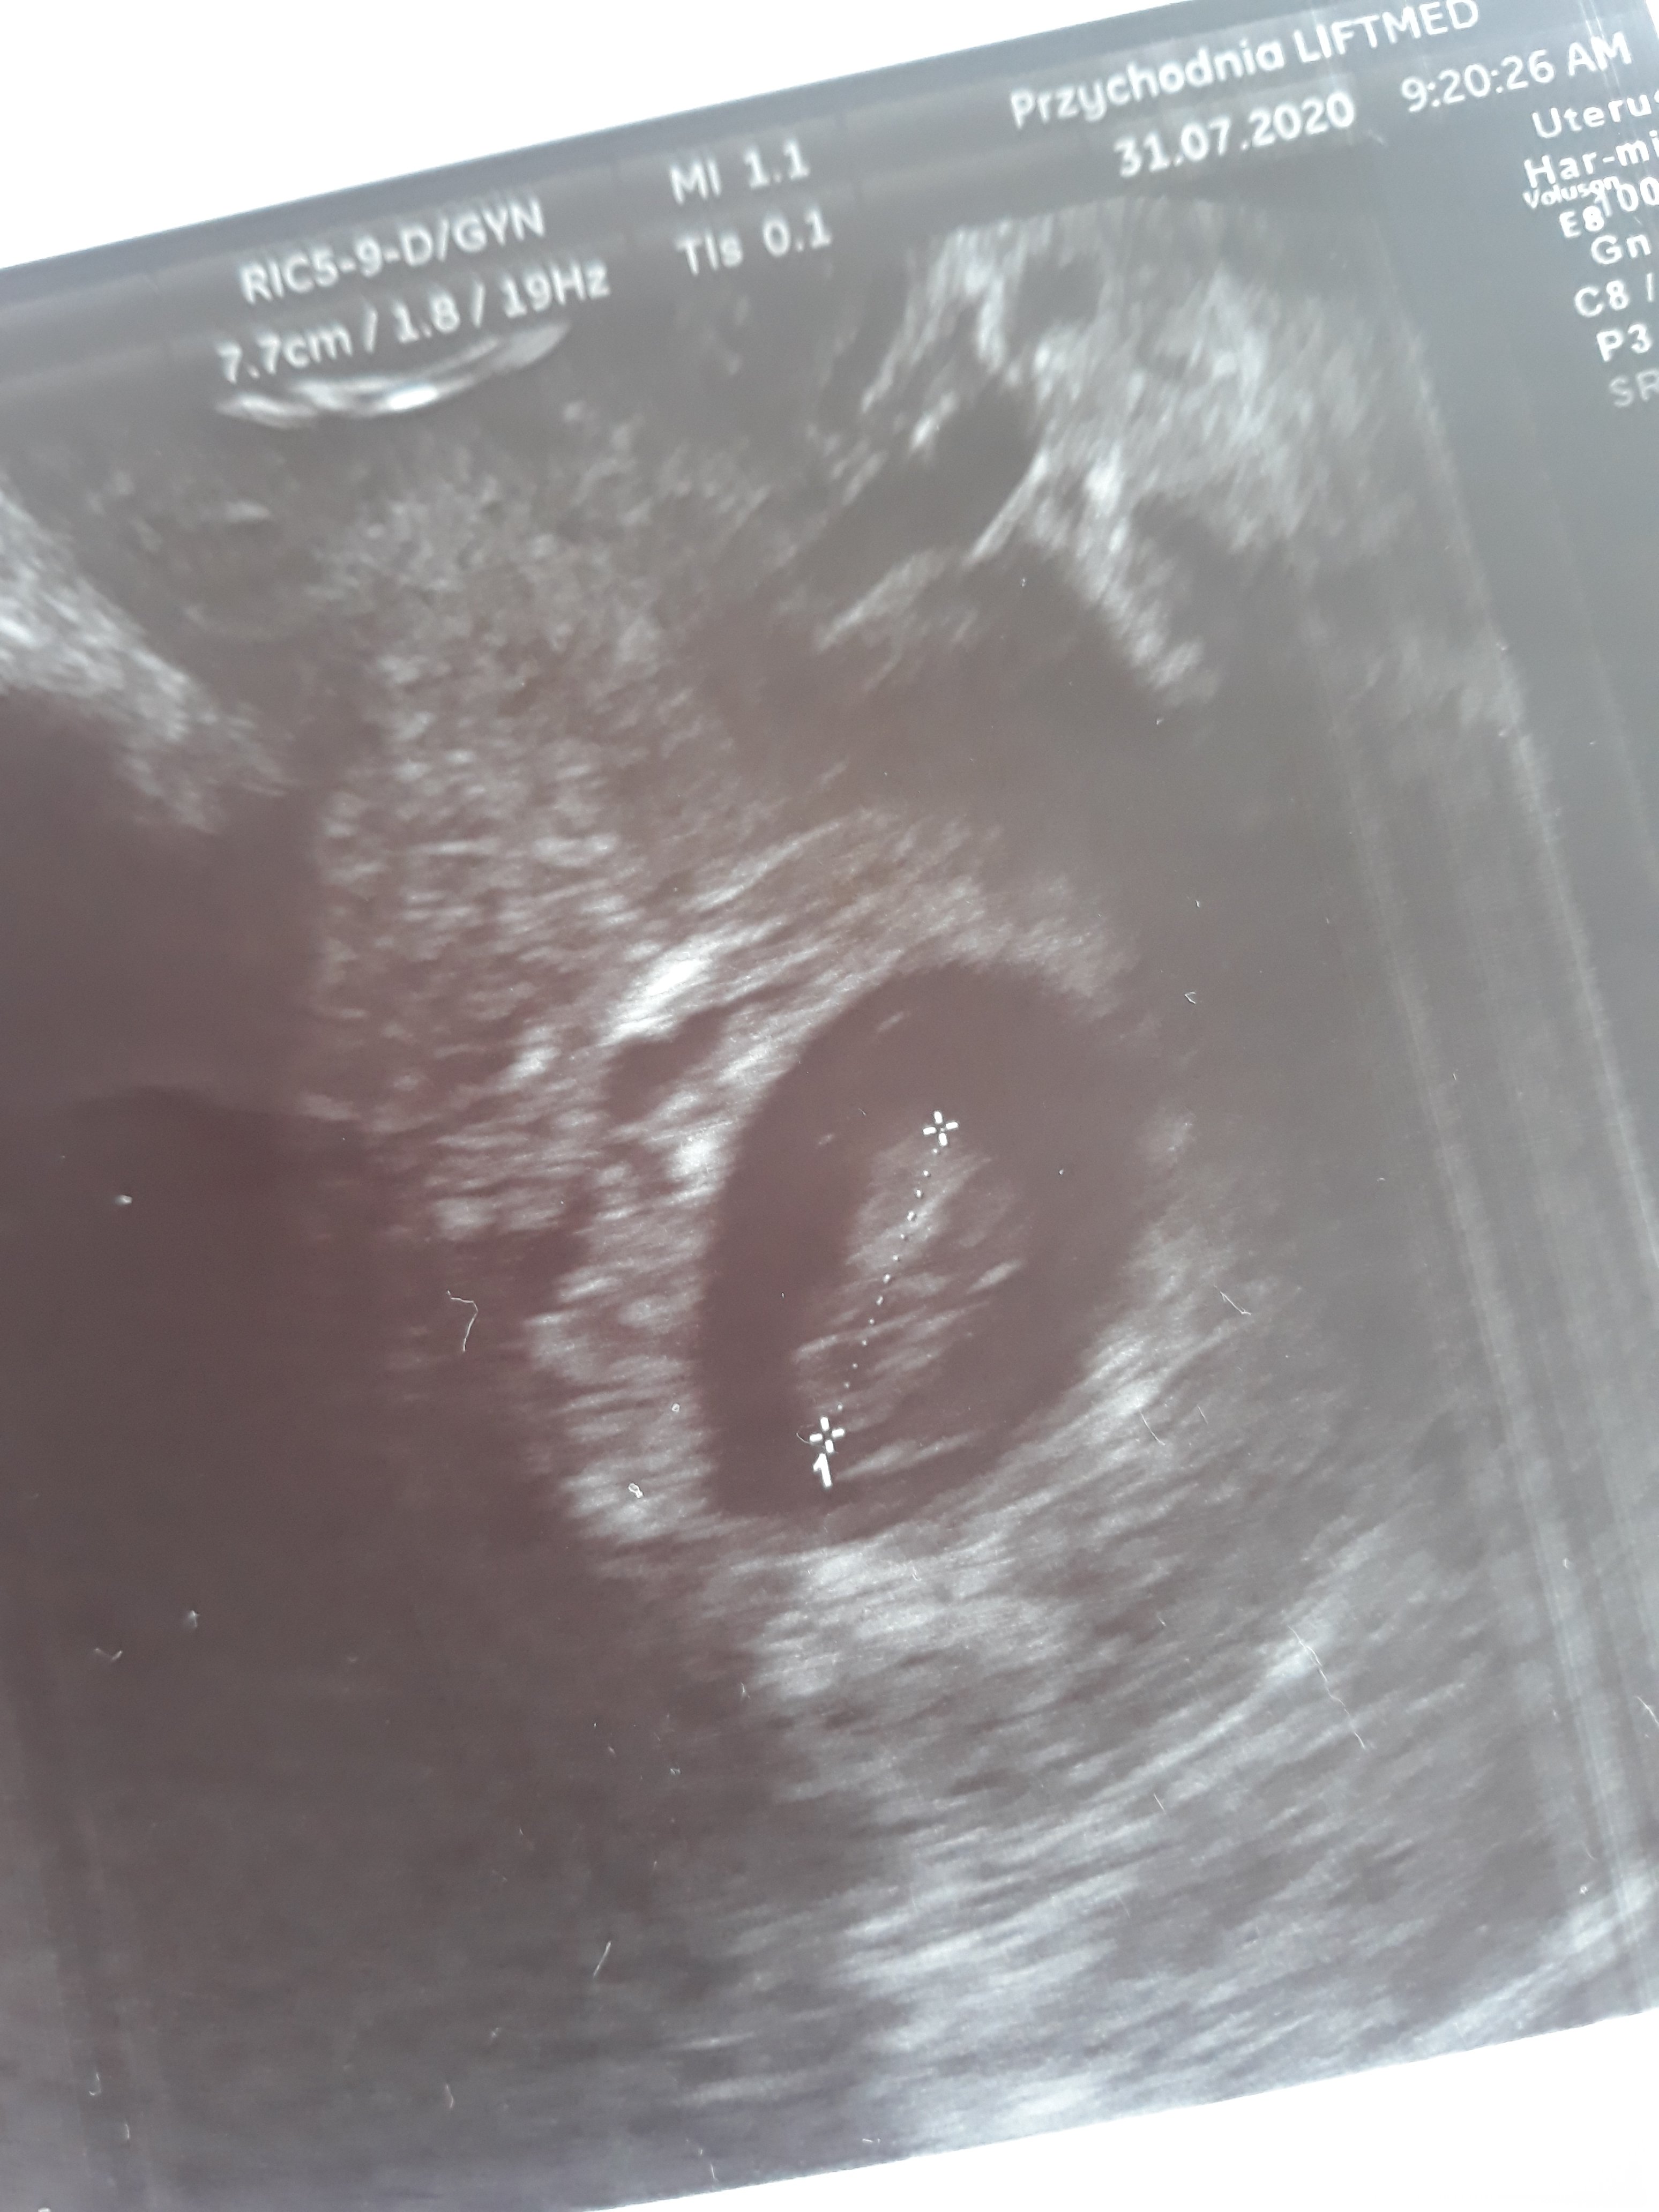

Piekna fasoleczka 9 tydztermin na 3-4 marca

juz macha glowka jak szalone hehe

Zobacz załącznik 1156279

Super zdrówka życzę dla wasJezu dziewczyny, stresu przeżyłam niesamowitego zwłaszcza że ostatnie dni w pracy dały mi popalić I czułam się w ogóle bardzo średnio. Ale udało mi się wbić do innego lekarza, zrobił mi usg I widziałam moją fasolkę która ma już prawie 1.5cm. Nie do końca wiadomo skąd krwawienie bo powodów może być sporo ale póki co dostałam L4 i luteine. Mam nadzieję że będzie dobrzeod razu jakiś taki weekend spokojniejszy a i przy okazji krwawienie ustało